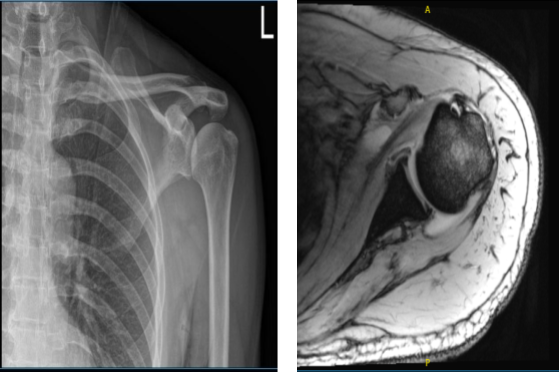

The patient was seen by me in the office with complaints of shoulder pain following an accident. His X-ray showed No abnormal soft tissue calcification is present.

Acromioclavicular joint reveals no significant abnormalities. The patient was treated conservatively, but failed. An MRI was done, which showed a rotator cuff tear of the left shoulder.

MRI of the left shoulder